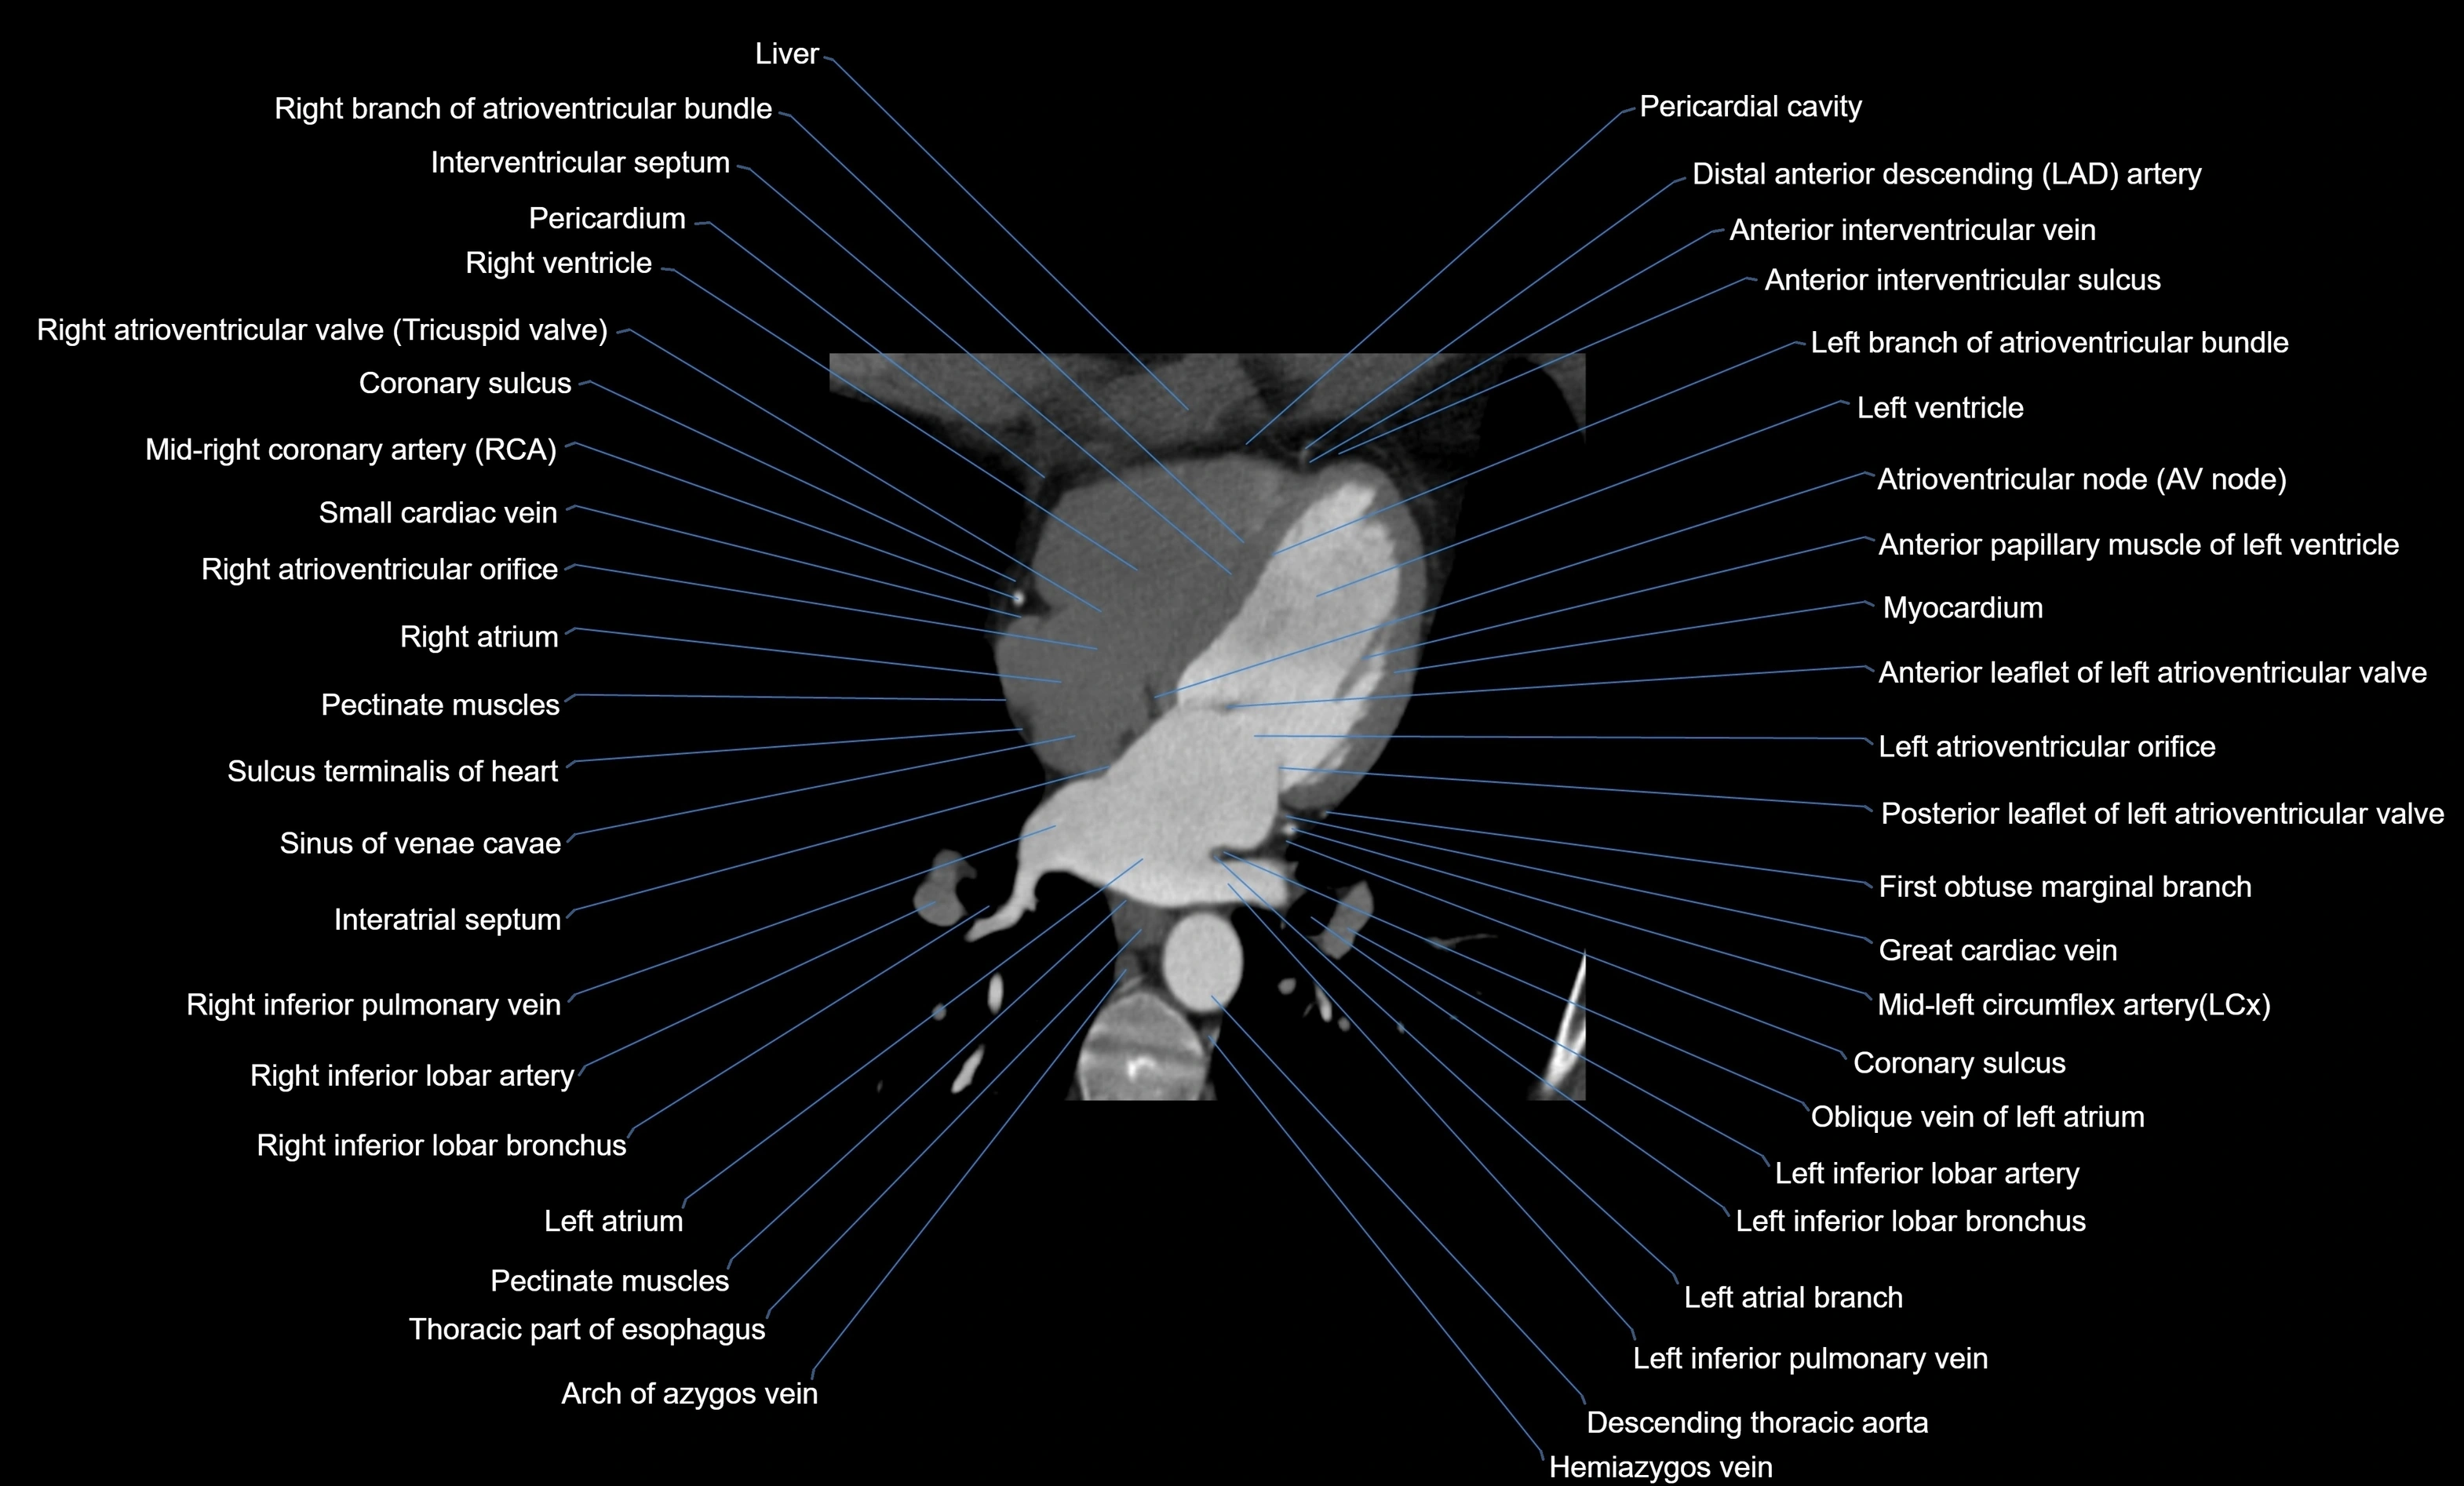

- Anterior leaflet of left atrioventricular valve

- Atrioventricular Node (AV Node)

- Coronary sulcus

- First obtuse marginal branch

- Great cardiac vein

- Hemiazygos vein

- Interatrial septum

- Interventricular Septum

- Left anterior descending artery (LAD)

- Left atrial branch (coronary artery)

- Left atrioventricular valve (mitral or bicuspid valve)

- Left atrium

- Left branch of atrioventricular bundle

- Left inferior pulmonary vein

- Left ventricle

- Middle cardiac vein

- Myocardium

- Oblique vein of left atrium

- Pectinate muscles

- Posterior leaflet of left atrioventricular valve

- Right atrioventricular valve (tricuspid valve)

- Right atrium

- Right branch of atrioventricular bundle

- Right inferior pulmonary vein

- Right ventricle

- Sinus of venae cavae (sinus venarum)

- Small cardiac vein

- Sulcus terminalis of heart